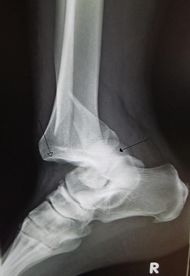

| An traumatic dislocation of the tibiotalar joint of the ankle with distal fibular fracture. Open arrow marks the tibia and the closed arrow marks the talus. | |